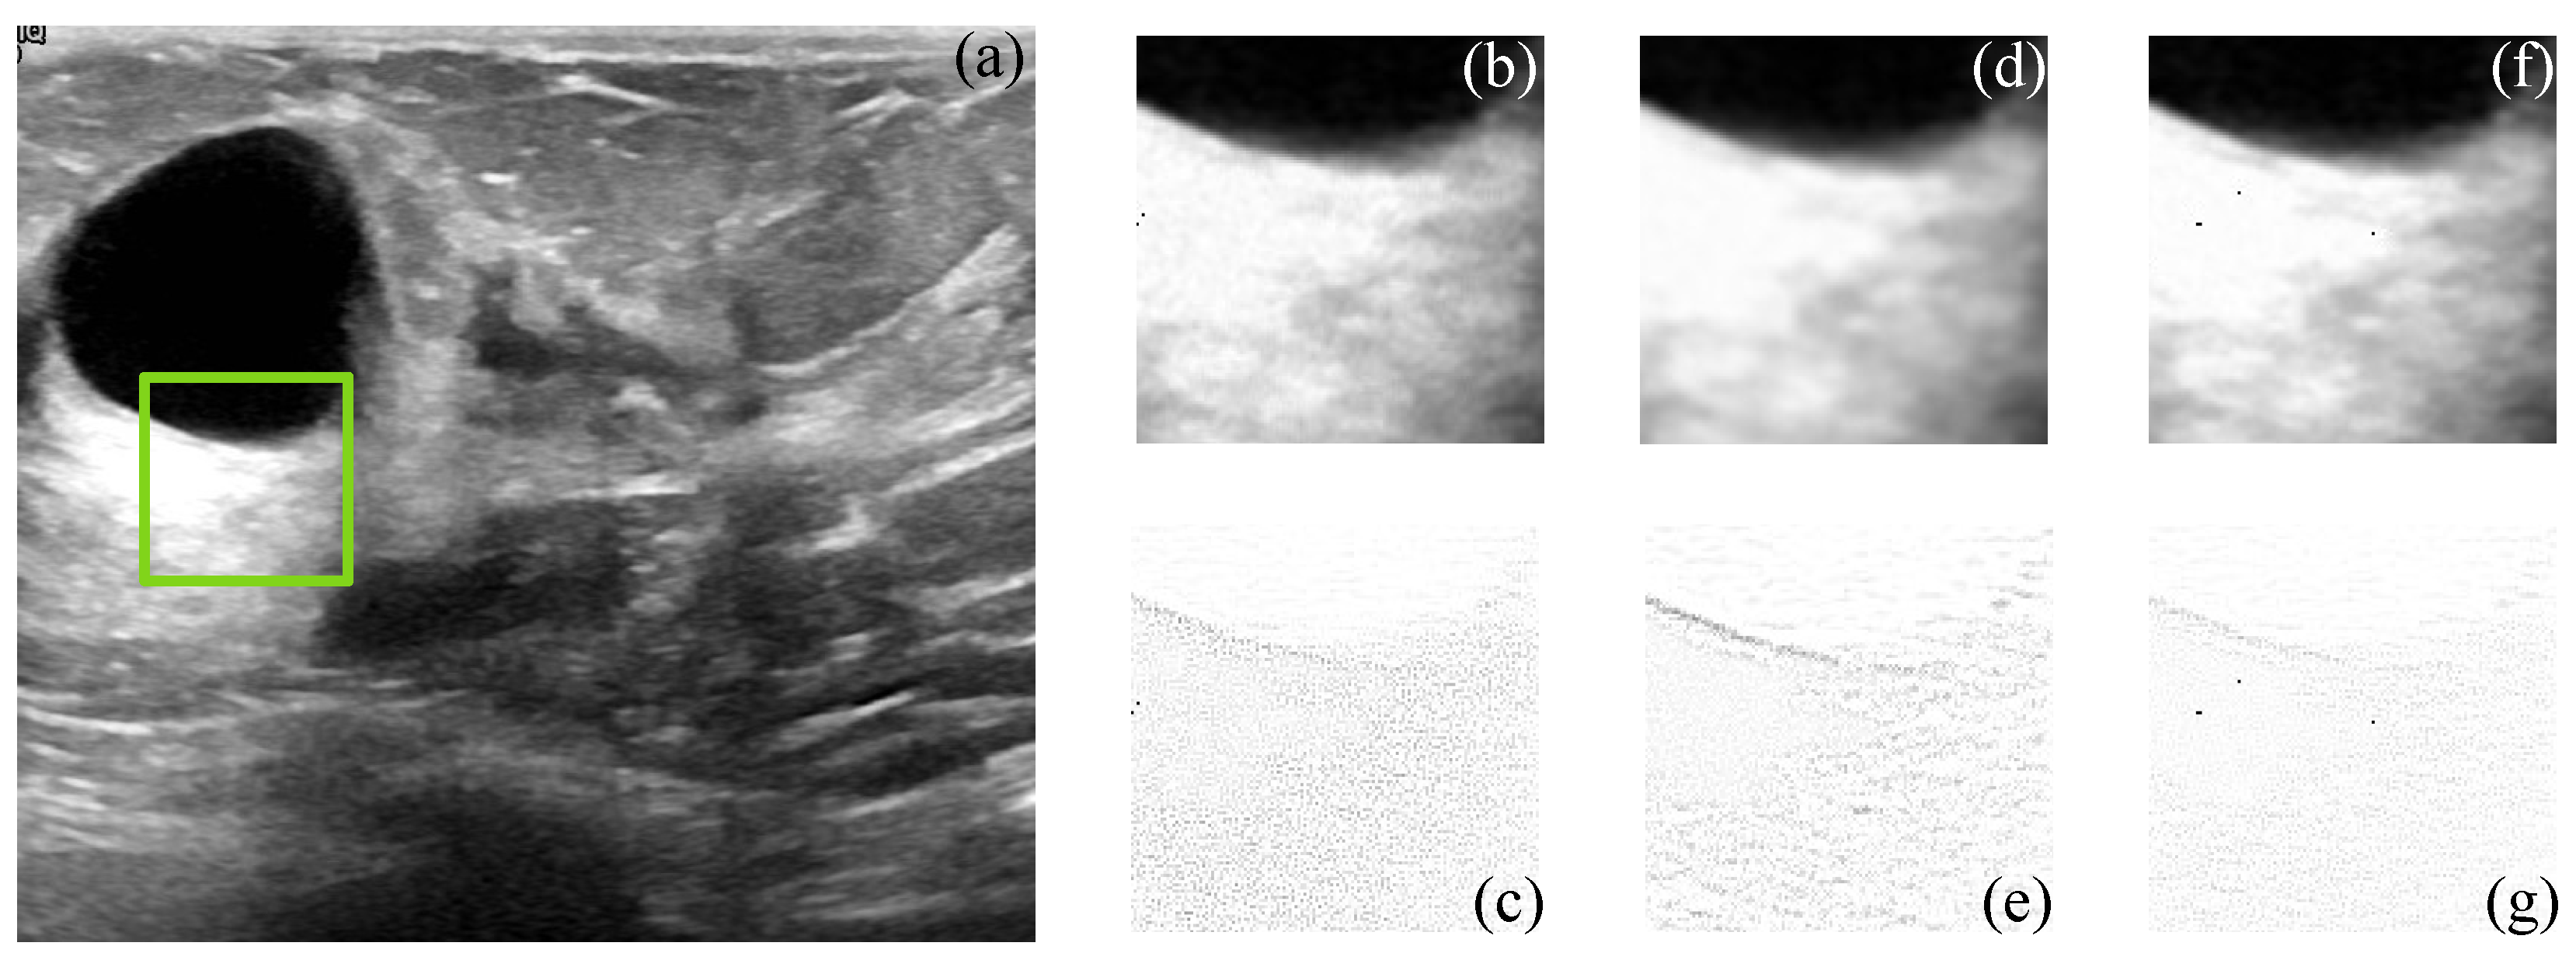

Figure 9 and Figure 10 show the actual filtered ultrasound images, named US-07 and US-20, respectively, with the subjective visual comparison of the proposed CMI-3DSVD against the BM3D and DLRA methods.

Figure 9 and Figure 10 show that the proposed approach provides high-quality despeckled images compared to the BM3D and DLRA methods. Moreover, as noticed in the error images, the DLRA filter causes blurring in detailed areas. This drawback resides in the lack of consideration of statistical properties for 3D group creation and the use of the Euclidean distance to measure the similarity between patches, which may cause alteration of the edges’ properties of the processed 3D block. In opposition, the CMI-3DSVD filter achieves better performance since it preserves edge quality and does not deform homogeneous regions in the processed images.

Figure 9. Subjective visual results of the despeckled real US image US-07. (a) Input image. Details are taken from the region marked in green: BM3D: (b) despeckled image, PSNR = 26.57 dB, EPI = 0.7164; (c) error image. DLRA: (d) despeckled image, PSNR = 26.92 dB, EPI = 0.8275; (e) error image. CMI-3DSVD: (f) despeckled image, PSNR = 27.10 dB, EPI = 0.8641; (g) error image.